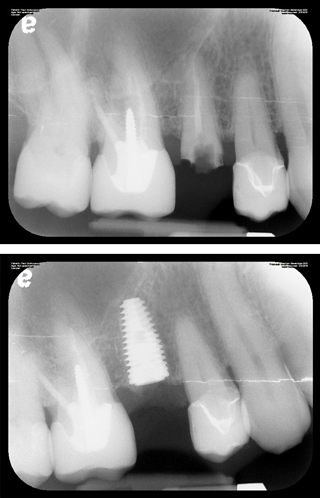

A dental implant is a tooth replacement solution made up of three parts: a small titanium screw carefully placed into the jawbone, an abutment that connects to it above the gumline, and a custom dental crown on top that looks and functions like a natural tooth. Once the implant fuses with the bone through a natural process called osseointegration, it creates a stable, permanent foundation for a custom crown, bridge, or denture on top.

A dental implant is the only replacement option that puts something back into the bone. The titanium post stimulates the jaw the same way a natural root does, which halts bone loss and keeps the surrounding teeth stable. Bridges and dentures sit on top of the gum and do nothing to address what’s happening underneath.